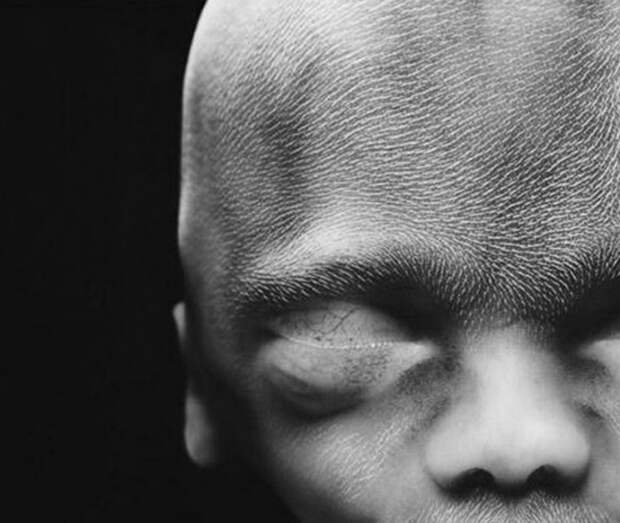

13. 10 недель. Веки уже полуоткрыты.

14. 16 недель.

15. Сквозь тонкую кожу видна сеть кровеносных сосудов.

16. 18 недель. Зародыш может воспринимать звуки из внешнего мира.